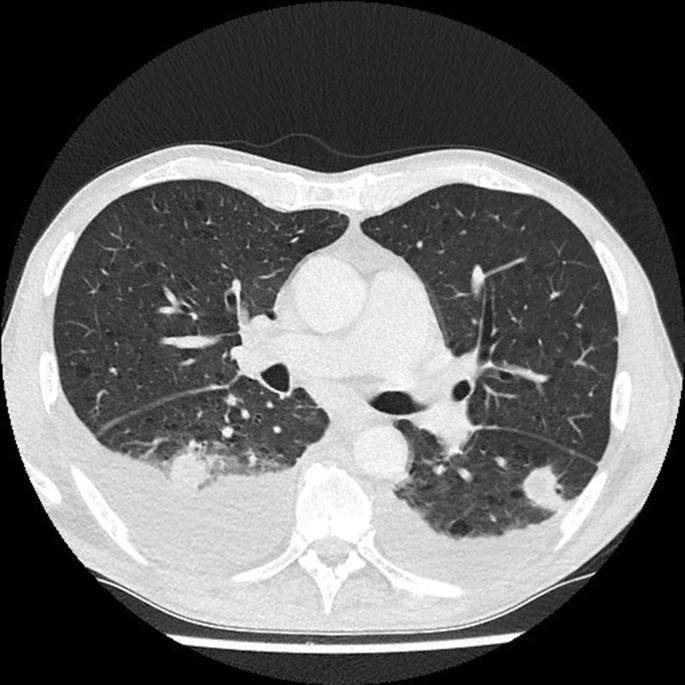

Tularemia is a rare zoonotic disease caused by the two predominant subspecies of Francisella tularensis, namely subspecies tularensis and subspecies holarctica. The latter is less virulent than the former, is endemic in Europe, and usually has a mild disease course, although respiratory involvement and bacteraemia can occur. Tularemia in Belgium is rare, but the incidence seems to be increasing. It therefore seems prudent to raise awareness among clinicians for this potentially severe disease. We report the first case of pneumonic tularemia with bacteraemia from Belgium, and want to recommend including Francisella tularensis in the differential diagnosis of pneumonia when an unfavorable evolution is seen with standard treatment.

兔热病是一种罕见的人畜共患病,由土拉弗朗西斯菌的两个主要亚种引起,即土拉弗朗西斯菌亚种和全北区亚种。后者的毒力低于前者,在欧洲呈地方性流行,通常病程较轻,尽管可出现肺部受累和菌血症。兔热病在比利时较为罕见,但发病率似乎在上升。因此,提高临床医生对这种潜在严重疾病的认识似乎是明智的。我们报告了比利时首例伴有菌血症的肺型兔热病病例,并建议在标准治疗效果不佳时,将土拉弗朗西斯菌纳入肺炎的鉴别诊断。